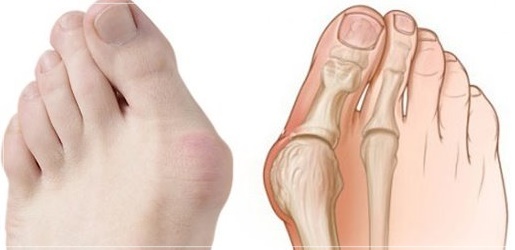

무지외반증은 엄지발가락이 둘째발가락 쪽으로 심하게 휘어져 엄지발가락 관절이 안쪽으로 돌출된 상태를 말하며, 심한 경우에는 엄지발가락이 둘째발가락과 엇갈리는 정도까지 돌아가기도 합니다. 특히 앞이 좁고 굽이 높은 신발을 자주 신는 여성에 흔한 대표적인 족부 질환입니다.

엄지 발가락의 튀어나온 관절부분(건막류)이 신발에 눌려 통증을 호소하는 것이 주 증상이나 엄지발가락이 둘째발가락 쪽으로 휘어져 있고, 관절이 안쪽으로 돌출되어 있습니다. 돌출된 관절은 서 있거나 걸을 때 자극을 받아 빨갛게 변하고 굳은살이 잡히며 염증과 통증이 발생합니다. 엄지발가락이 제 역할을 하지 못하니 발의 다른 부위에도 통증이 생기고 심해지면 발 모양의 변형, 허리의 통증 등이 발생합니다.